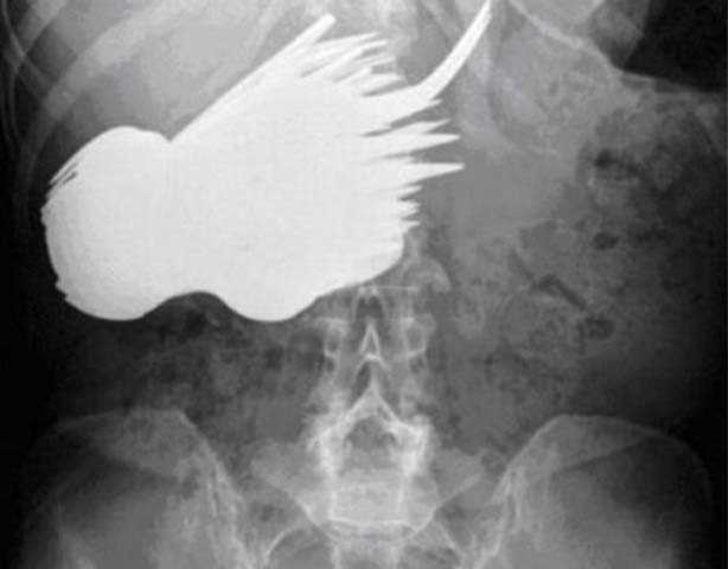

Pil ve yatak yayı

Tutuklular, hastaneye gidebilmek ya da hapishaneye kaçak olarak sokabilmek için bazen çok acayip şeyler yutabiliyor. Amerika'nın Kuzey Karolina eyaletindeki bir hapishanede bulunan tutuklular, hastaneye gönderilme umuduyla pil ve yatak yayı yutmuşlar. Her iki tutuklu da denemesinde başarılı oldu; yukarıda, karın ağrısı şikayetiyle gittikleri hastanede çekilen röntgenleri görüyorsunuz.